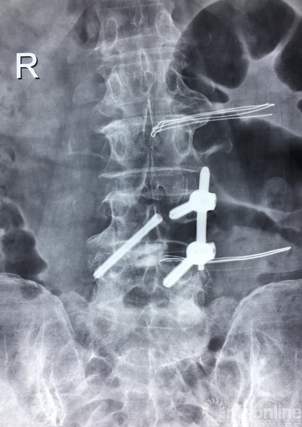

术后正、侧位片

术后三维SCT确认融合器,钉棒植入位置满意